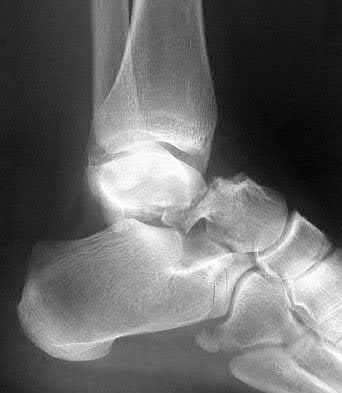

A 34-year-old male sustains the closed injury seen in Figure A as a result of a high-speed motor vehicle collision. What is the most appropriate next step in treatment?

The radiograph shows a comminuted pilon fracture, which is associated with high-energy trauma and significant soft tissue injury. The tested concept here is the importance of avoiding definitive reduction and fixation of this high-energy injury, which has been shown to be associated with an increased risk of wound complications and deep infections (as compared to staged treatment with usage of a spanning external fixator).